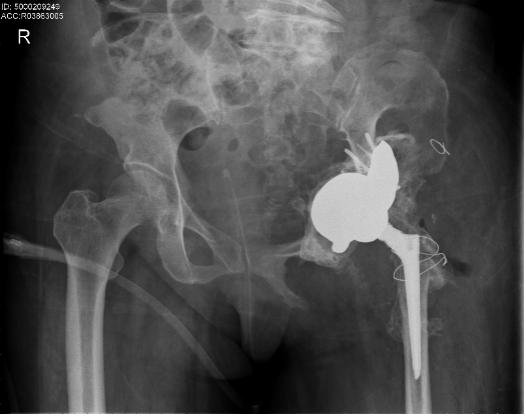

2022年4,南方医科大学第五附属医院(下简称“南医五院”)骨肿瘤专科成功开展手术切除髋关节并通过3D打印假体,帮助患者功能重建。术后复查,髋关节活动正常。

盆骨也会长肿瘤吗?广州市民方先生刚刚退休,之前因为甲状腺癌复发,在市区手术治疗后左边髋关节疼痛不已,扛了半年时间越来越疼回医院检查。没想到按下葫芦浮起瓢,影像检查发现甲状腺癌转移到盆骨。方先生找到南医五院骨肿瘤专科主任钟华博士,确诊为盆骨髋臼部位肿瘤,而且放任下去可能发生病理性骨折,丧失正常行走功能。

南医五院骨肿瘤规范化治疗团队与广东省人民医院骨肿瘤科团队组织讨论,为患者制定了术前3D打印个性化半骨盆假体及精准截骨导板,术前介入栓塞骨肿瘤及周围的供血动脉围手术期准备下的骨盆切除髋关节功能重建手术。

经过约6个小时,手术精准切除了髋臼区的肿瘤并重建了髋关节的功能。虽然出血量控制在正常范围,但手术为患者输血超2000ml,接近成年男子体内一半的血量,患者术后恢复良好。